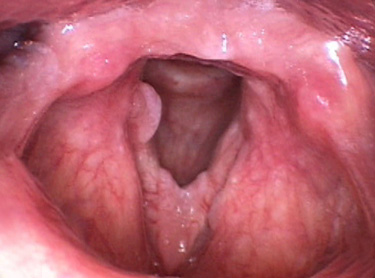

후두유두종 증상

초기에 쉰 목소리가 나타나며 단발성은 정상 상피가 단순히 이식증식을 일으킨 것이고 다발성 유두종은 소아에게 주로 발생하며 재발이 심하고

넓게 분포가 되어 있으면 호흡곤란증세가 올 수 있습니다.